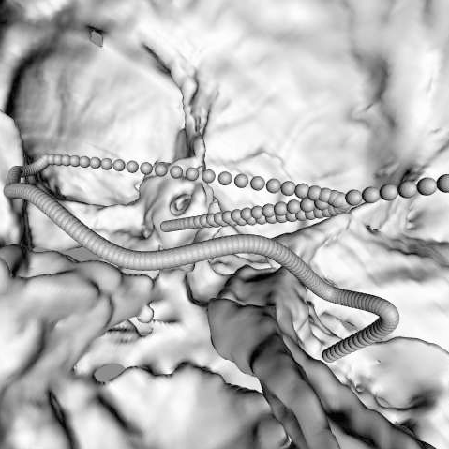

Virtual Voyage

Virtual Instrument Flight